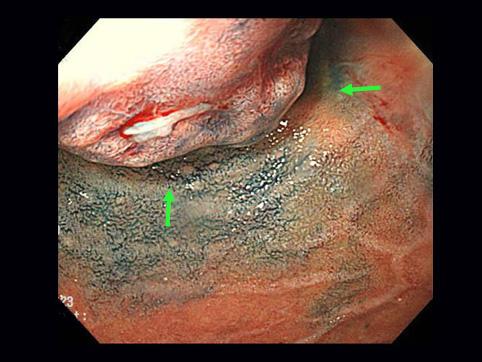

A case of carcinoid tumor which developed in the duodenal bulb.

[Image-ID:11490]

카시노이드종양/

십이지장/구부

1형(종괴형)/

15~19